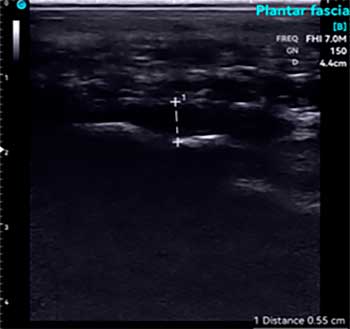

La utilización de un ecógrafo para diagnosticar la fasciosis plantar es esencial y es la herramienta más idónea para su examen.

En ecografía observamos una señal hipoecoica con separación de las fibras de la fascia plantar. El valor normal de fascia plantar sana es de 3mm. Es importante realizar un estudio ecográfico comparativo en el otro pie para visualizar el rango de grosor de la otra fascia.

A continuación adjunto varios casos de imágenes ecográficas con fasciopatía plantar: